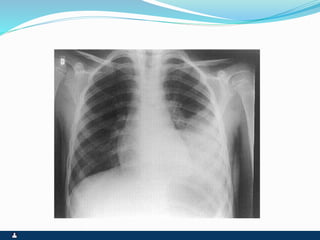

PNEUMOTÓRAX

RUPTURA DE UM DOS FOLHETOS

SINTOMAS SINAIS

 PRIMÁRIO ( ESPONTÂNEO

) SECUNDÁRIO(

TRAUMA,IATROGÊNICO )

 INÍCIO SÚBITO

 DOR PLEURÍCA INTENSA

 TOSSE SECA

 DISPNÉIA

 FACIES DE DOENÇA

AGUDA,ANSIEDADE E

SUDORESE

 EXPANSIBILIDADE REDUZIDA

 DESVIO CONTRALATERAL DO

MEDIASTINO

 ABAULAMENTO

HOMOLATERAL DOS

ESPAÇOS INTERCOSTAIS

 FTV ABOLIDO

 TIMPANISMO

 MV ABOLIDO

 RUIDOS ADVENTÍCIOS

AUSENTES

 ENFISEMA SUBCUTÂNEO

EVENTUAL